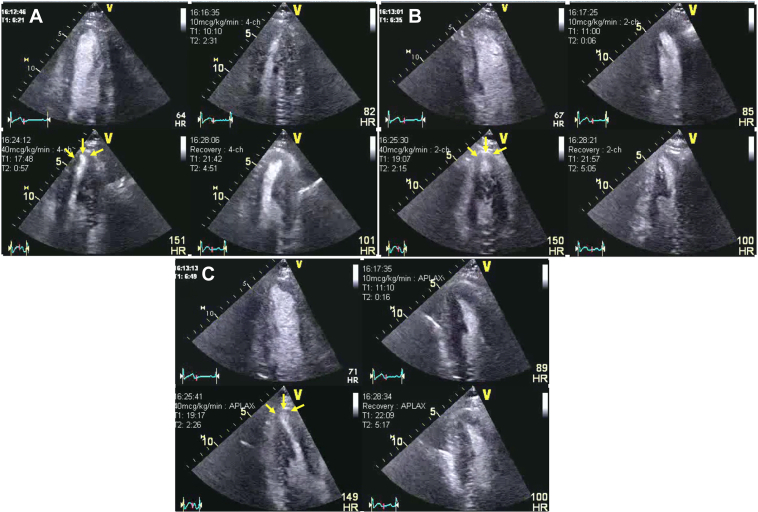

A 42-year-old man with a known family history of premature CAD and a current smoker was referred for ongoing typical chest pain for DSE after his ICA showed nonobstructive CAD (Figure 10). His DSE was terminated at the end of protocol at 85% of age-predicted maximal heart rate (at the end of 40 μg/kg/min and 1 mg atropine in addition to handgrip exercise). The rate-pressure product was 26,727 mm Hg·beats/min. At the peak test, the patient developed nonlimiting chest pain that was quick to resolve spontaneously in the recovery. The resting echocardiogram showed no RWMA, and all segments of the left ventricle augmented well during low dose. During peak stress the apical segment became thin and dyskinetic associated with the chest pain. The CFV in the distal LAD was 33 cm/s and 77 cm/s at baseline and peak, respectively, in keeping with a normal CFVR (3.35) (Figures 11 and 12, Video 4). The patient was recommended lifestyle modification and guideline-directed medical therapy. A diagnosis of coronary vasospasm was entertained.

Figure 10.

Patient 3: Dobutamine Stress Echocardiography

Dobutamine stress echocardiography with ultrasound enhancing agent, end-systolic frames at different views and stages. (A) Apical 4-chamber view. (B) Apical 2-chamber view. (C) Apical 3-chamber view. The quad images represent the resting, low-dose, peak stress, and recovery stages of the protocol. The yellow arrow indicates small area of apical thinning and dyskinesis at peak stress in all the views. The changes in apical kinesis can be more appreciated if the same regions are compared between low dose and peak stress.

Patient 3: DSE

Dobutamine stress echocardiography (DSE) at different views and stages. (A) Apical 4-chamber view. (B) Apical 2-chamber view. (C) Apical 3-chamber view. The quad images represent the resting, low-dose, peak stress and recovery stages of the protocol. The yellow arrows indicate a small area of apical thinning and dyskinesis at peak stress in all the views. The changes in apical kinesis can be more appreciated if the same regions are compared between low-dose and peak stress.